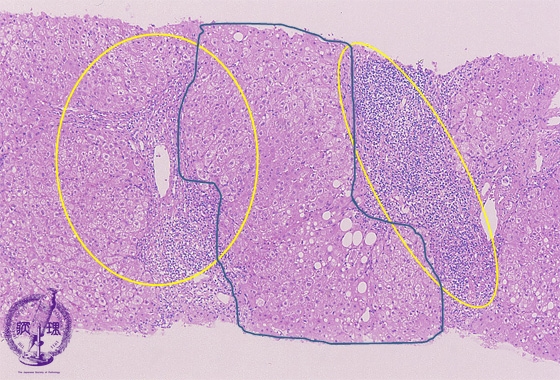

Microscopic image (HE stain, low power view): There is a dense lymphocytic infiltrate with corresponding moderate to marked portal expansion (yellow circle). Fibrosis (blue line) is also seen, and results in disruption of the lobular architecture with segregation of lobules which imparts a nodular appearance in some areas (blue area).